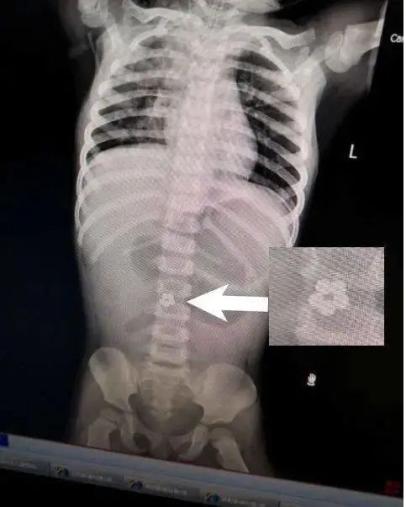

可是,住院治疗“肠胃炎”两天后,小静还是一直吐。一天下来,少说也要吐个十次八次。眼见治疗没效果,医生让孩子拍片检查。这一查居然发现,小静肚子里有5个连成圈的小球!

打开腹腔后,医生终于找到了磁力球排不出来的原因:这5个小球分布在不同的肠段,但却牢牢地吸在一起。医生小心地取出小磁球,再把穿孔的肠道切除,最后进行了缝合。整个手术足足花了2个小时。